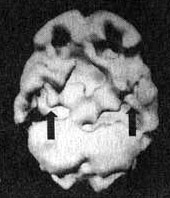

3. С помощью SPECT можно получить информацию, помогающую врачу добиться понимания и сострадания к пациенту у членов его семьи. Фрэнк — состоятельный, хорошо образованный человек. Вскоре после того как ему исполнилось 70 лет, он стал забывчивым. Сначала он забывал мелочи, но со временем провалы в памяти стали прогрессировать, и он начал забывать значимые факты собственной биографии: где он живет, как зовут его жену и даже как зовут его самого. Жена и дети были не в состоянии понять, чем вызваны такие перемены, а его рассеянность и забывчивость их нередко раздражали. Результаты SPECT показали, что у Фрэнка на всей поверхности мозга отмечается резкое снижение активности, и особенно во фронтальных, париетальных и височных долях. Это была классическая картина синдрома Альцгеймера. Показав семье снимки и объяснив, что забывчивость Фрэнка имеет четкую физиологическую природу, я помог им осознать, что он не специально раздражает их, а серьезно болен. Впоследствии, вместо того чтобы упрекать его за забывчивость, близкие Фрэнка стали поддерживать его и разработали схемы, позволившие эффективнее бороться с трудностями, возникающими у всякого, кто вынужден жить рядом с человеком, страдающим болезнью Альцгеймера.

Мозг Фрэнка — болезнь Альцгеймера

Трехмерное изображение поверхности, вид сверху

Трехмерное изображение нижней поверхности

Обратите внимание на выраженное общее снижение активности, особенно в париетальных долях (см. стрелки, рис. слева) и в височных долях (см. стрелки, рис. справа).